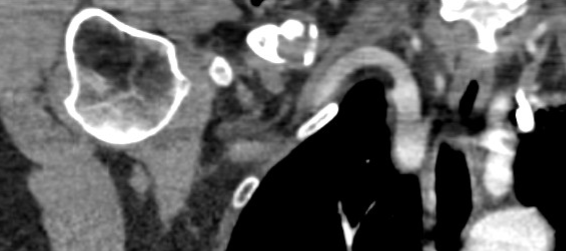

Vascular injury

CT scan: green circle - clavicle nonunion, red arrows - subclavian artery, blue arrow - subclavian vein

Subclavian vein injury

Subclavian vein may be adhered to periosteum medially

- instrumentation medially and inferiorly must be subperiosteal

- careful with medial screws